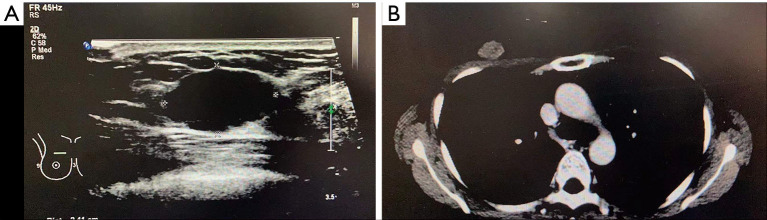

Case description: A 45-year-old female presented with a painless mass in the medial-upper quadrants of right breast and the imaging examination suggested a malignant tumor. She received modified radical mastectomy and axillary sentinel lymph node dissection of the right breast, and the pathological diagnosis was squamous cell carcinoma with HER2 over-expression. Subsequently, she underwent post-operative chemotherapy regimen of doxorubicin, cyclophosphamide, T-docetaxel and trastuzumab (AC-TH) and then received maintenance treatment with trastuzumab and pertuzumab. Clinical follow-up suggests that she had achieved clinical complete remission and has survived for over 4 years.